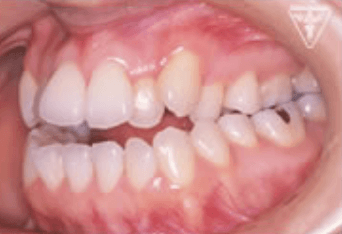

治療前、装置装着直後

治療後

治療前後の比較